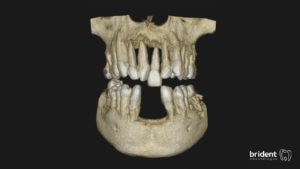

Tras un examen clínico y en algunos casos la realización de un Tac dental 3D o una Ortopantomografía, nuestro experto en periodoncia llevará a cabo una valoración y un plan de tratamiento personalizado para cada paciente.

1. DIAGNÓSTICO

Realizamos radiografías o un tac 3D y una serie de pruebas clínicas con una sonda periodontal para diagnosticar si existe enfermedad periodontal o no.